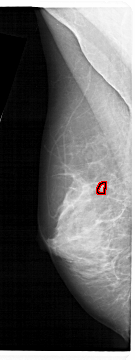

ics_version 1.0 filename A-1591-1 DATE_OF_STUDY 14 8 1990 PATIENT_AGE 52 FILM FILM_TYPE REGULAR DENSITY 4 DATE_DIGITIZED 7 1 1999 DIGITIZER HOWTEK 43.5 SEQUENCE LEFT_CC LINES 5131 PIXELS_PER_LINE 1531 BITS_PER_PIXEL 12 RESOLUTION 43.5 OVERLAY LEFT_MLO LINES 5386 PIXELS_PER_LINE 2011 BITS_PER_PIXEL 12 RESOLUTION 43.5 OVERLAY RIGHT_CC LINES 4651 PIXELS_PER_LINE 2011 BITS_PER_PIXEL 12 RESOLUTION 43.5 NON_OVERLAY RIGHT_MLO LINES 5296 PIXELS_PER_LINE 2206 BITS_PER_PIXEL 12 RESOLUTION 43.5 NON_OVERLAY |

FILE: A_1591_1.LEFT_MLO.OVERLAY TOTAL_ABNORMALITIES 1 ABNORMALITY 1 LESION_TYPE CALCIFICATION TYPE PLEOMORPHIC DISTRIBUTION CLUSTERED ASSESSMENT 4 SUBTLETY 1 PATHOLOGY MALIGNANT TOTAL_OUTLINES 1 BOUNDARY |

FILE: A_1591_1.LEFT_CC.OVERLAY TOTAL_ABNORMALITIES 1 ABNORMALITY 1 LESION_TYPE CALCIFICATION TYPE PLEOMORPHIC DISTRIBUTION CLUSTERED ASSESSMENT 4 SUBTLETY 1 PATHOLOGY MALIGNANT TOTAL_OUTLINES 1 BOUNDARY |